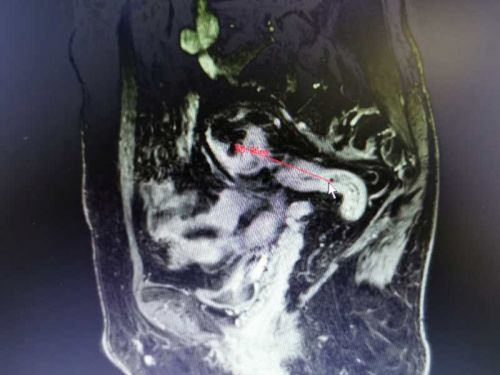

乙状结肠肿瘤

通过多项检查诊断技术全面评估肿瘤部位及患者全身状况, CTMRI(普美显)提示患者乙状结肠癌并肝脏寡转移瘤,结直肠肛门外科、肝胆外科、放射科、肿瘤科、病理科开展晚期结直肠癌MDT讨论认为,患者乙状结肠癌肝转移合并不完全性肠梗阻,暂不适合术前新辅助化疗,有乙状结肠癌和肝转移瘤同时R0切除手术机会,但同时切除手术难度及风险增加。

在与患者及家属充分沟通交流后,为患者制定术前处理、手术切除、术中监测、术后治疗和康复方案,由肖志刚主任团队施行目前结直肠癌专科最微创的手术方式——腹腔镜下乙状结肠癌根治性切除+S5段转移瘤切除,经阴道取出标本的NOSES手术(腹壁切口<1cm)。术中请肝胆外科杨建辉副主任医师同台行肝S5段转移瘤切除。手术过程顺利,患者术后无伤口疼痛,术后第1天下床活动,术后第2天肛门排气,第3天排便并恢复流质饮食,第6天复查CT腹腔干净并拔除腹腔引流管,第8天康复出院,电话随访患者状态良好。